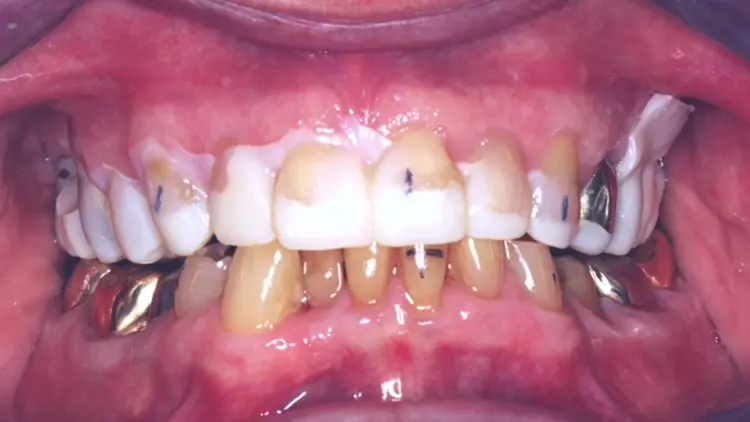

Ihr Videofilm dokumentiert die Rehabilitation des frakturierten Frontzahns 12 sowie der verloren gegangenen Vertikaldimension aufgrund erosiven Zahnhartsubstanz-Verlustes bei einem 75-jährigen Patienten. Die Behandlung wurde in 3 Bisshebungsphasen gegliedert. Gezeigt wurde die digitale Herstellung einer Polycarbonatschiene sowie eines non-prep Langzeitprovisoriums aus Hybridkeramik.Während der Tragephase der Schiene können sowohl Daten für die finale Versorgung gesammelt sowie Änderungen hinsichtlich Phonetik, Ästhetik oder Funktion vorgenommen werden. Durch die Hinterlegung der Datensätze sind auch Modifikationen bei der Gestaltung des LZP sowie der späteren keramischen Versorgung jederzeit möglich.

Aini, Awiszus, Bornmann